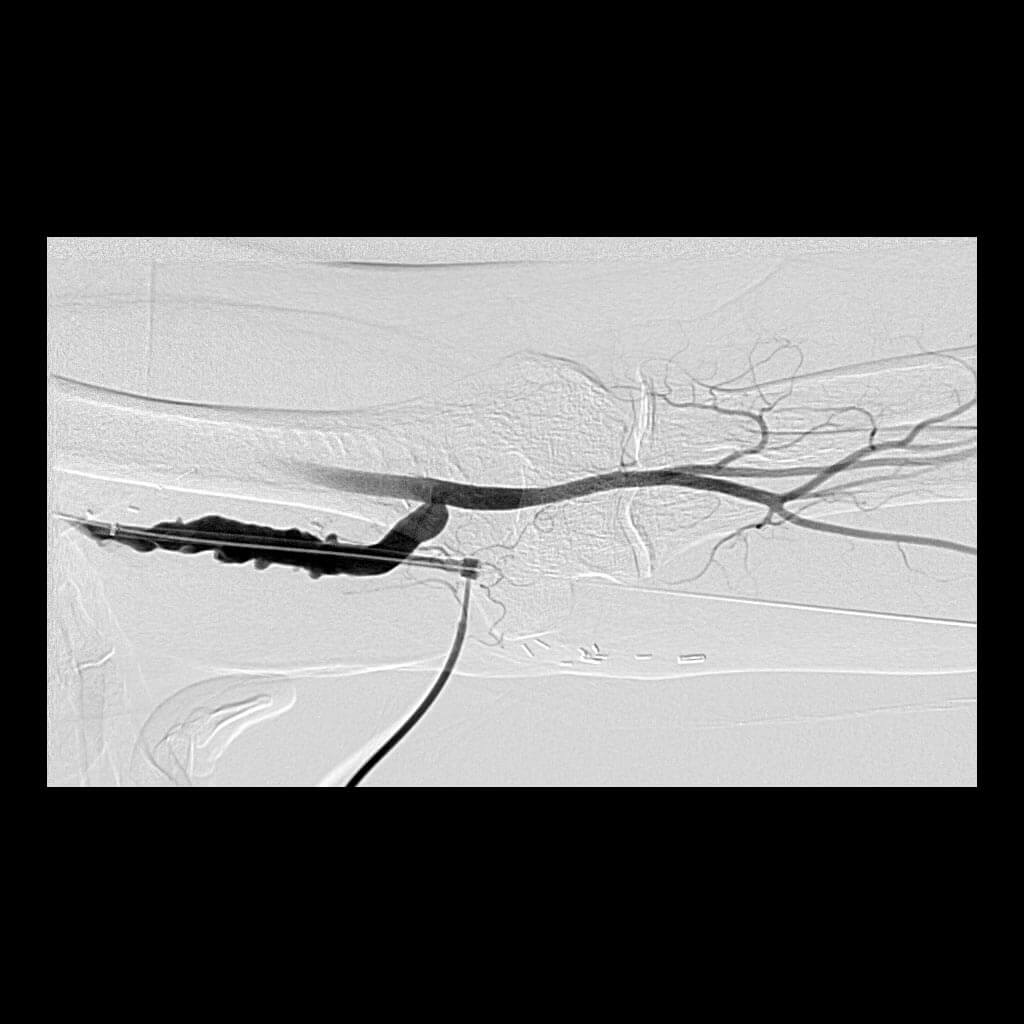

Dialysis Fistula & Graft Interventions

Patients receiving hemodialysis receive this treatment through surgically created dialysis grafts and fistulas. Over time, the function of these conduits may diminish, which can impact the effectiveness of dialysis. IR regularly performs procedures to preserve the patency and functionality of AV dialysis grafts and fistulas.